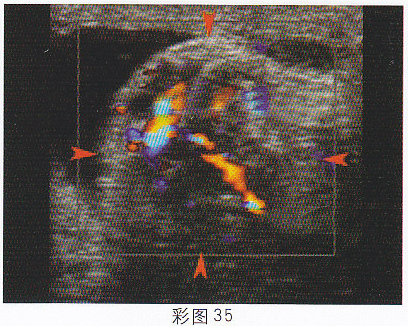

4.根據超聲圖像(彩圖35),最可能的診斷為

正確答案:A 解題思路:附睪腫大,可見低回聲光團,形態不規則。